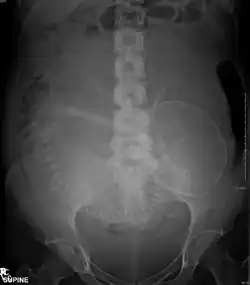

Radiografia e medicina nuclear

Efeitos fetais por dose de radiação

Os efeitos da radiação sobre a saúde podem ser agrupados em duas categorias gerais:

Doses fetais por método de imagem

| Método de imagem | Dose absorvida fetal de radiação ionizante (mGy) |

|---|---|

| Radiografia projetiva | |

| Abdome | 0.1 - 3.0[1] |

| Coluna lombar | 1.0 - 10[1] |

| Urografia excretora | 5 - 10[1] |

| Enema opaco com duplo contraste | 1.0 - 20[1] |